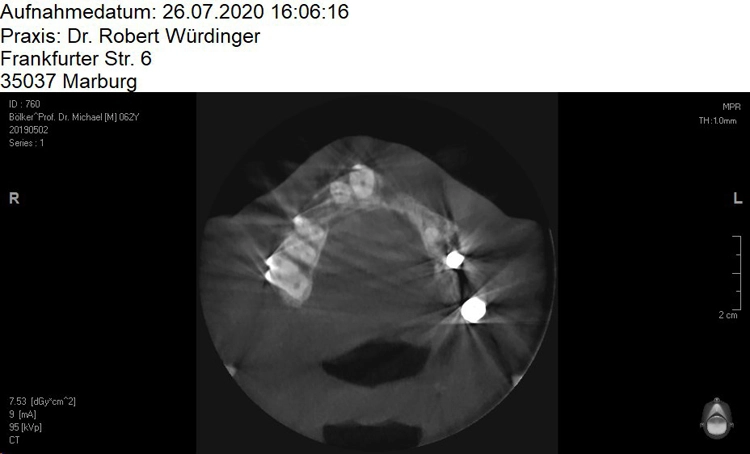

Ein 64 Jahre alter männlicher Patient ohne anamnestische Auffälligkeiten wurde mit dem Wunsch nach einer festsitzenden und ästhetisch ansprechenden Lösung im Frontzahnbereich von seinem Hauszahnarzt zur weiteren implantologischen Rehabilitation an unsere Praxis überwiesen. Nach eingehender klinischer Untersuchung wurde anhand einer 3D-Röntgenaufnahme mittels DVT das knöcherne Lager in der zu behandelnden Region beurteilt, worauf sich ein ausgeprägtes horizontales Knochendefizit zeigte, das eine Implantation in korrekter prothetischer Lage nicht zuließ (Abb. 1-3).

Die Entscheidung fiel daraufhin auf ein zweizeitiges Vorgehen mit vorheriger Knochenaugmentation in Schalentechnik und späterer Implantation von zwei BLT-Implantaten mit augmentativem Relining: Der Patient entschied sich nach ausführlicher Beratung und Vorstellung der alternativen Augmentationsmöglichkeiten für die Schalentechnik mit allogenen Kortikalisplatten und Granulaten (maxgraft® spongiosa, Straumann), wie die Abbildungen 4 bis 7 dokumentieren.